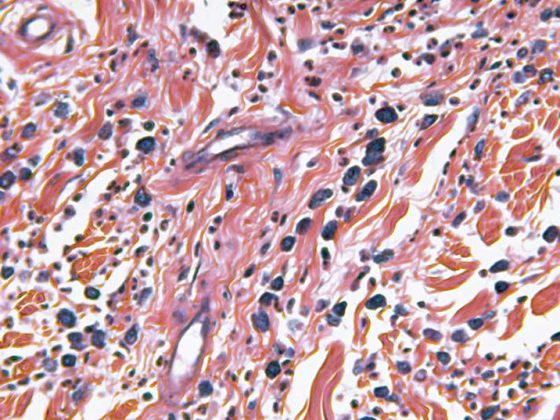

La principal indicación para la PS es el alivio del “sufrimiento insoportable”. Sin embargo, este término tampoco se define de manera uniforme o en absoluto en la literatura [2]. En este contexto, existen debates éticos en torno a la cuestión de si el sufrimiento físico insoportable puede equipararse al sufrimiento mental, social o espiritual (Fig. 1). En general, el término “sufrimiento insoportable” se refiere a un síntoma o afección mencionado por el paciente que no quiere soportar. La evaluación de una afección insoportable es principalmente responsabilidad de la persona afectada y es per se muy subjetiva en primera instancia, pero en algunos casos también pueden hacerla sus seres queridos o el equipo de tratamiento [8].